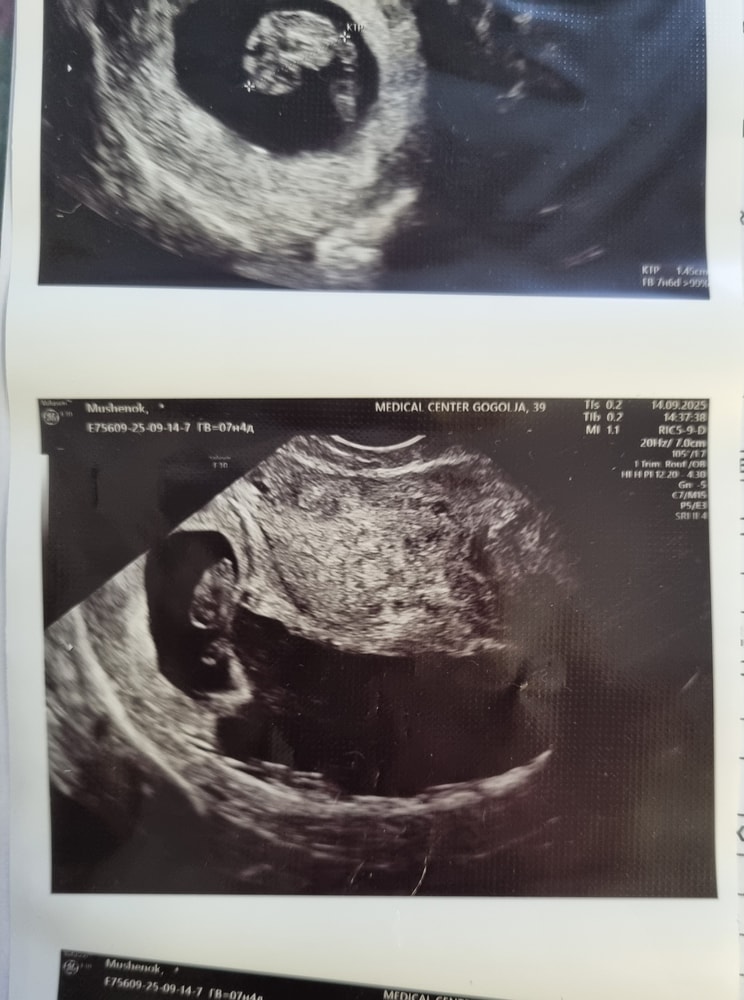

На таблетках и уколах😕 После б×б в следующем цикле вот такая беременность, с угрозой, отслойкой и огромной гематомой. С кровотечением приехала на скорой в больницу,лежу уже 8 дней. Неизвестно,что скажет врач завтра. Я прошла платно УЗИ в клинике. И вот какой результат

Что скажете,девочки? Как узист сказала, не вся часть хориона пришлась на отслойку,поэтому эмбрион живой. На что надеяться? Я не могу уже в больнице лежать😭начались головные боли,и с кишечником проблемы. В общем застои начались от нечегонеделания.

Ну гематома в стадии организации, это хорошо. Значит идет заживление. Больше лежите. Никаких физ нагрузок, нервов и прочее. Всё будет хорошо!